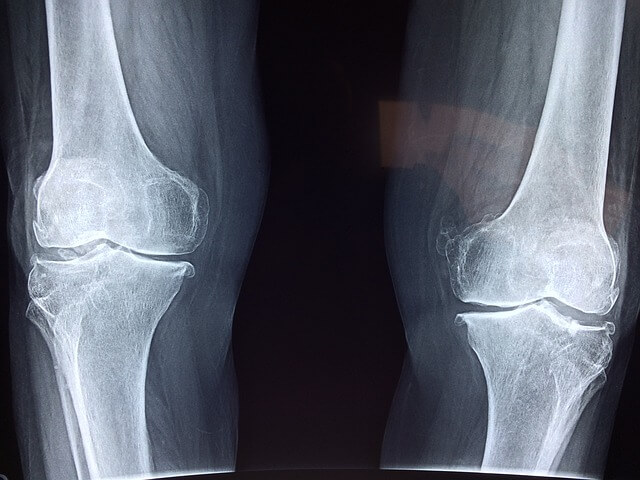

- 연골 보호 : 콘드로이친은 연골의 구조를 유지하고 손상을 방지하는 데 도움을 줍니다. 이는 관절의 기능을 향상하고 노화로 인한 연골 손실을 늦추는 데 기여합니다.